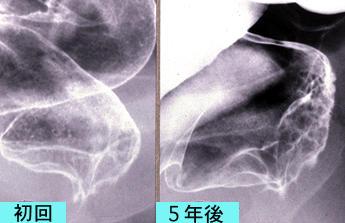

"Lesión nódulo agregante" del Recto en la que se evidenció avance lateral en la capa superficial

[Image-ID:1381]

parte(separada por órganos)

colon/recto

método de exámen

Rayos X

diámetro mayor del tumor

35 - 40